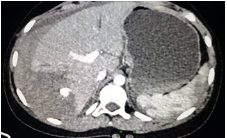

Contrast-enhanced CT of abdomen and pelvis revealed Grade IV liner laceration involving segments VI & VII of Right lobe of liver with 11 X 10mm pseudoaneurysm noted in segment VI/ VII of liver arising from post sectoral branch of right hepatic artery.

After stabilization, the patient was taken for transarterial embolization of pseudoaneurysm through the right femoral artery approach. Post-procedural angiogram revealed no flow into pseudoaneurysm and retained normal flow to the rest of the branches of the right and left hepatic arteries. Post-procedure period was uneventful.